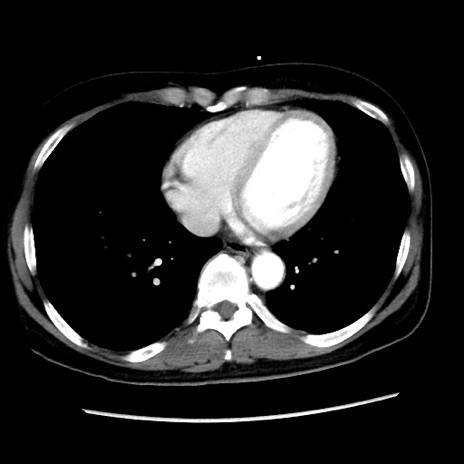

症例10(横断像)

【症例】 50歳代女性

【主訴】 腹痛

【現病歴】前日生レバーを食べた。今朝に排便あり。 昼前に突然発症の腹痛を生じ、当院救急外来を受診した。

【身体所見】 意識清明、腹部:平坦、軟、下腹部やや左を中心に圧痛・反跳痛あり、筋性防御あり

【データ】WBC 7800、CRP 0.07